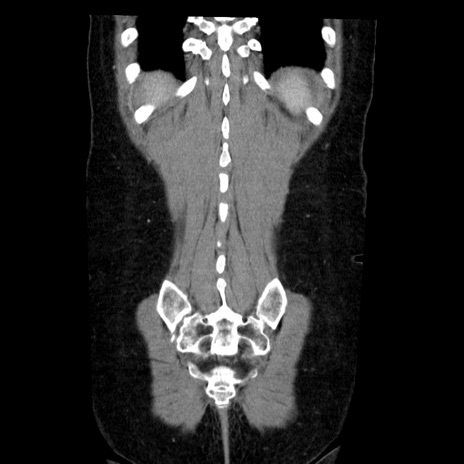

症例6(冠状断像)

【症例】50歳代女性

【主訴】下腹部痛

【現病歴】本日朝より下痢2回あり。 昼食を食べた後、嘔吐3回、下腹部痛認め、症状軽快せず、当院救急搬送。

最終食事:本日昼(生ものなし)。 昨日の夜、刺身を食ぺたとのこと。周囲に同様の症状の者なし。普段、排便は毎日あるとのこと。

【既往歴】卵巣癌術後(8年前に当院で卵巣摘出)

【身体所見】 意識清明、腹部:平坦、腸蠕動音→、やや硬、下腹部自発痛・圧痛あり、反跳痛あり、筋性防御なし。

【データ】WBC 16000、CRP 0.01